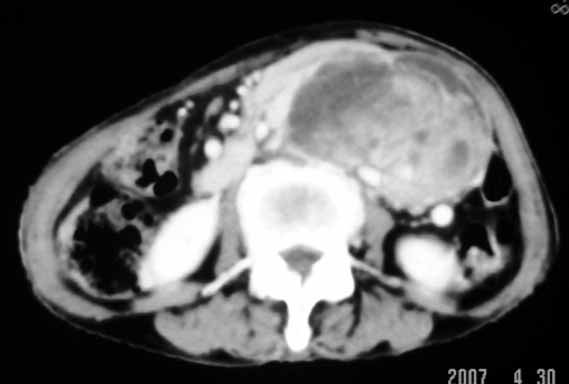

以下是引用天南地北在2007-4-30 17:42:00的发言:[br]增强扫描显示腹主动脉给包绕、推移。肿块不规则强化,[br]修正我在平扫的诊断[br]支持考虑:间叶源性肿瘤可能性大